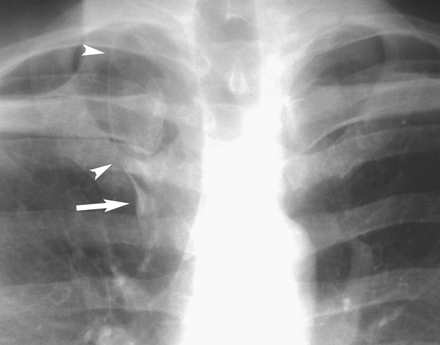

вот так, без выраженного затемнения